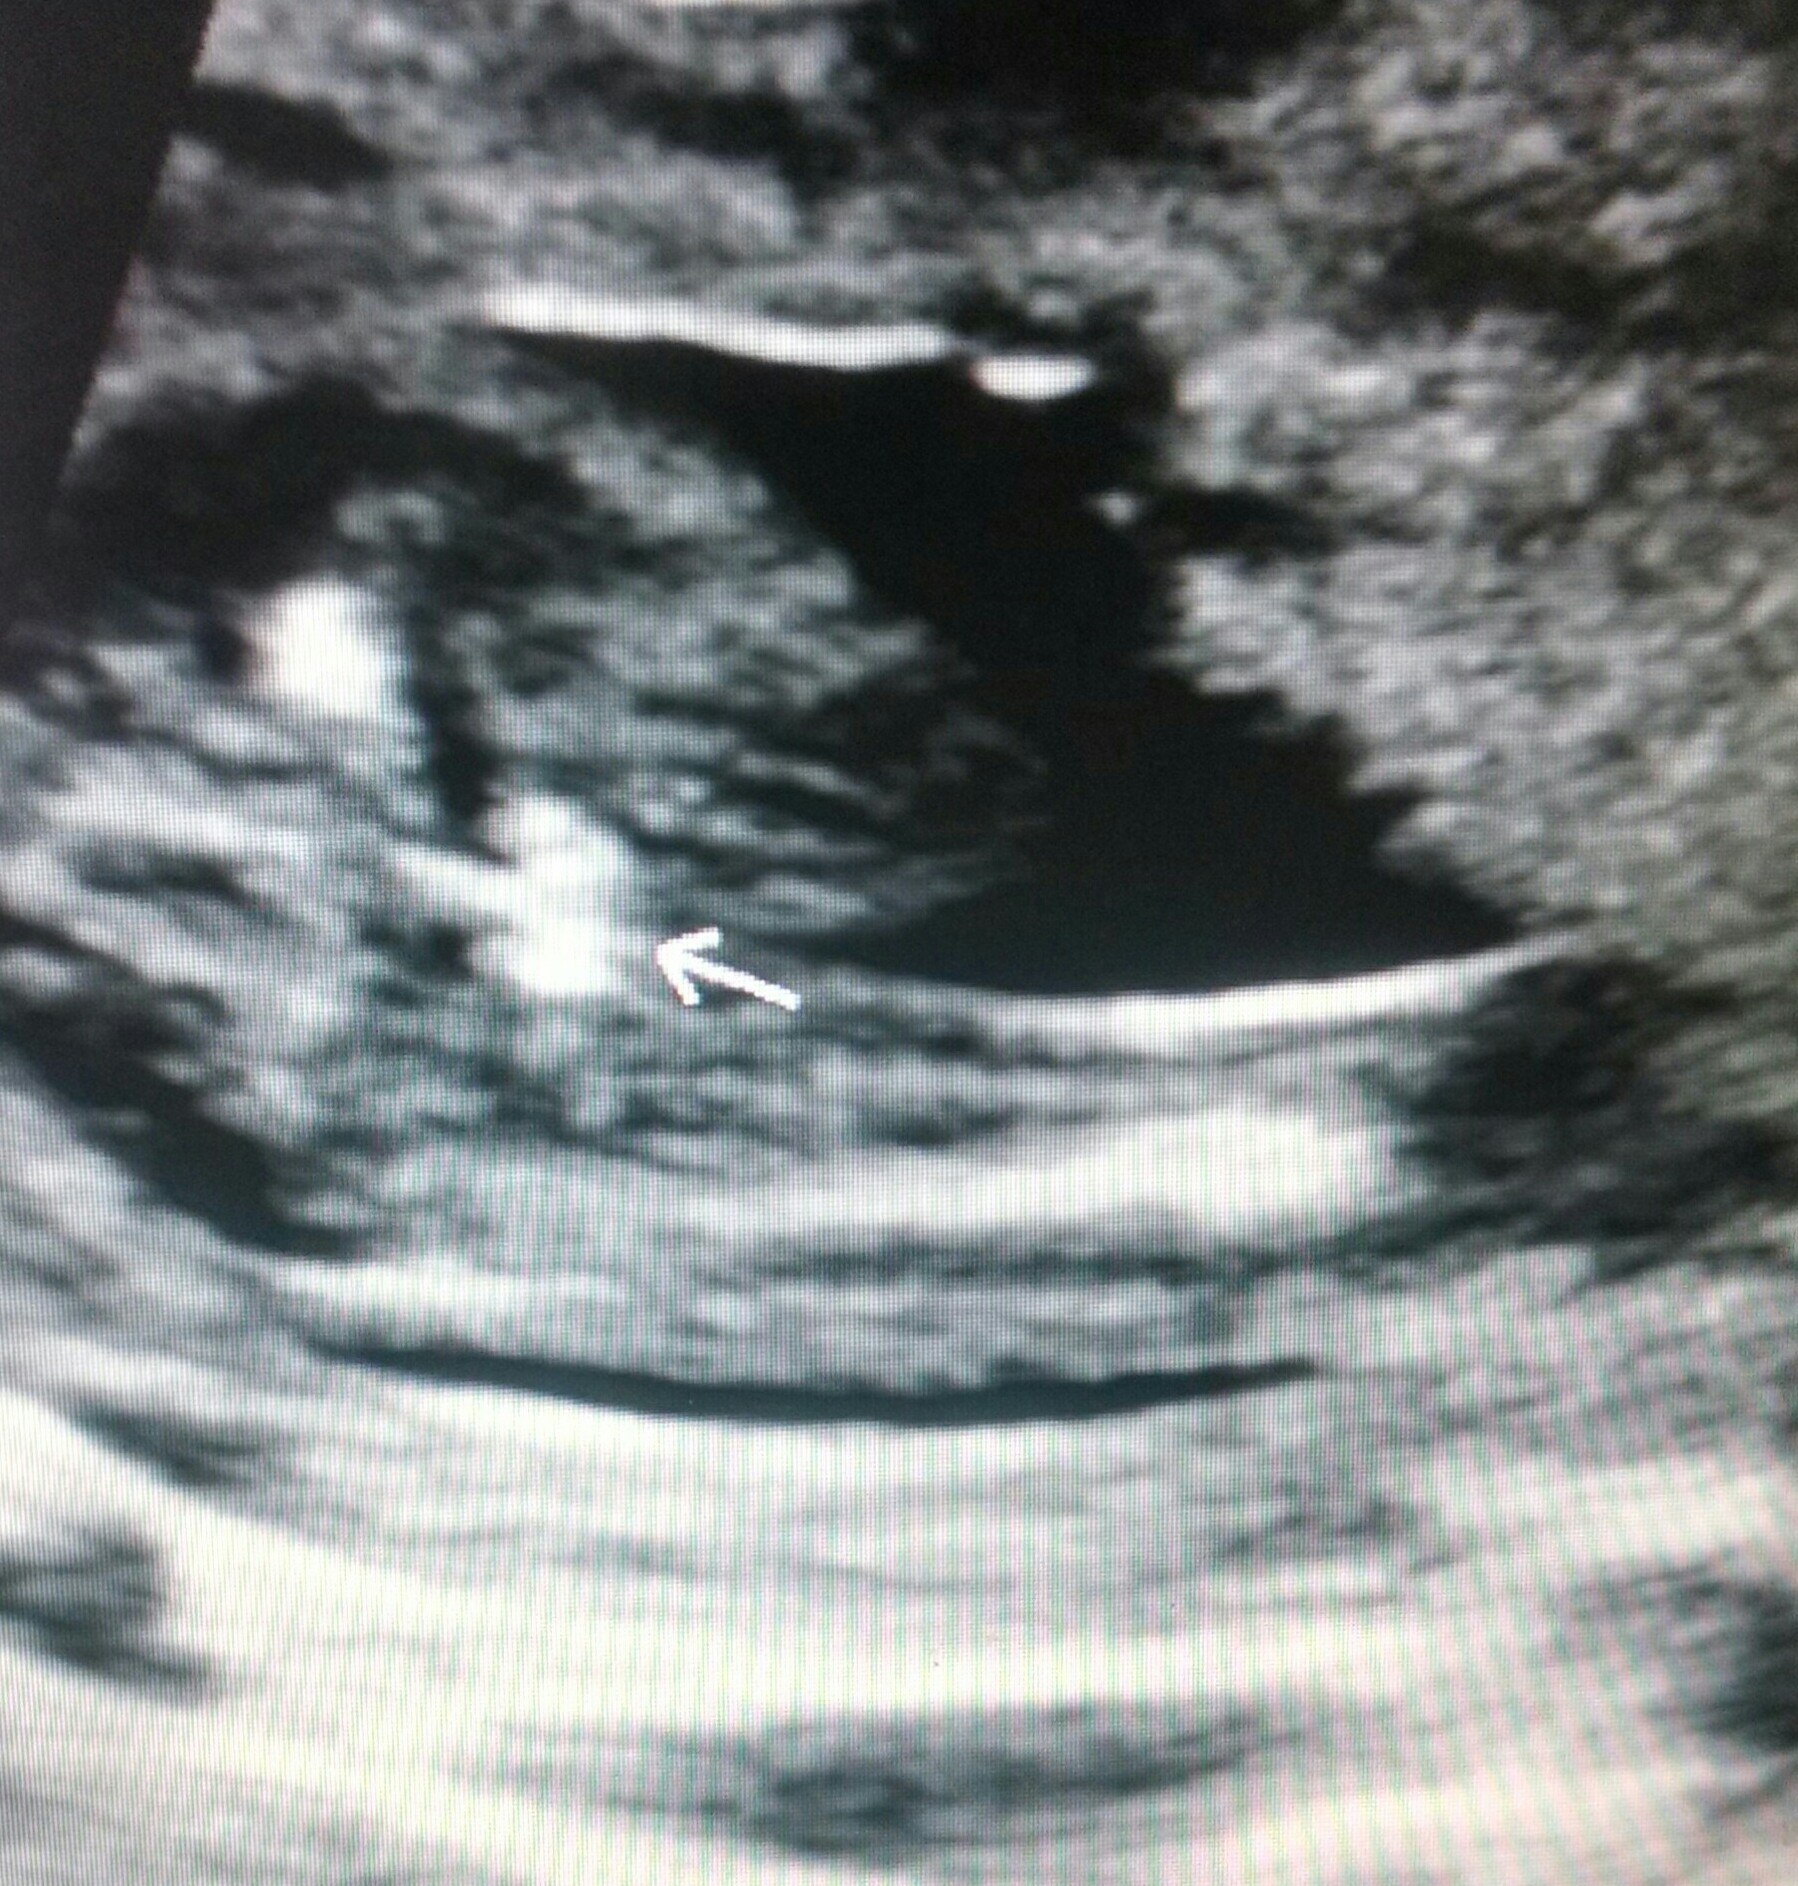

Tech wasn't 100% sure cause baby was on stomach and legs close together, I have 4 girls and was hoping this could by chance be a boy!! I was 19 weeks and 4 days! Thank you!!